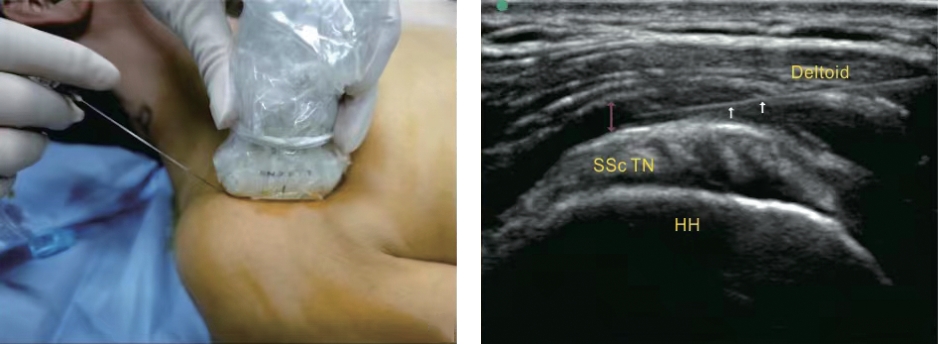

• 超声引导下肩关节囊周神经阻滞与肌间沟臂丛神经阻滞在肩关节镜术后恢复效果的比较

2026, 36(4):108-114. DOI: 10.3969/j.issn.1005-8982.2026.04.018

摘要 (68) HTML (14) PDF 843.66 K (39) 评论 (0) 收藏

摘要:目的 探讨超声引导下肩关节囊周神经阻滞(PENG)与肌间沟臂丛神经阻滞(ISB)在肩关节镜术后恢复的效果。方法 采用非劣效性研究设计,选取2023年1月—2024年6月于嘉兴市第二医院行单侧肩关节镜下肩袖修补手术的190例患者,按照区组随机化的方法随机分为PENG组、ISB组,各95例。术后PENG组失访6例,ISB组失访4例,最终研究纳入PENG组89例、ISB组91例。比较两组术后恢复质量评定量表(QoR-40)评分、疼痛数字评分量表(NRS)评分、第1次镇痛补救时间、镇痛补救率、术后镇痛泵按压次数、麻醉剂用量及不良反应。结果 PENG组治疗前与术后24 h QoR-40评分的差值小于ISB组(P <0.05)。PENG组与ISB组术后30 min和4、8、12、24、48 h静息状态NRS评分比较,结果 ①不同时间点NRS评分比较,差异有统计学意义(P <0.05);②PENG组与ISB组NRS评分比较,差异有统计学意义(P <0.05),PENG组NRS评分更低;③两组NRS评分变化趋势比较,差异有统计学意义(P <0.05)。PENG组补救镇痛率低于ISB组(P <0.05),镇痛泵按压次数少于ISB组(P <0.05)。PENG组术后反跳痛发生率低于ISB组(P <0.05)。结论 超声引导下肩关节PENG在肩关节镜术后的恢复效果与ISB相当;PENG对RCI患者可实现有效镇痛,且安全性良好。

• 0+1